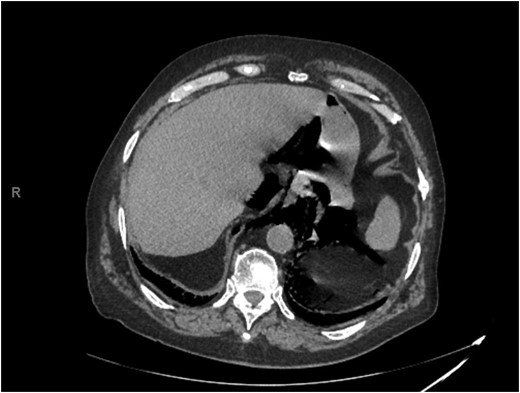

Abdominal CT showed pneumomediastinum and pneumoperitoneum secondary to perforated hollow viscus necessitating emergent exploratory laparotomy (Figs 1 and 2). Lysis of adhesions, right hemicolectomy with primary ileocolic anastomosis, and umbilical hernia repair were performed. NGT placement after induction of general anesthesia was noted to be difficult secondary to resistance met with advancement of the catheter. Postoperatively, the patient was transferred to the surgical intensive care unit (SICU) in stable condition.

Representative slice from abdominal computed tomography imaging on admission.